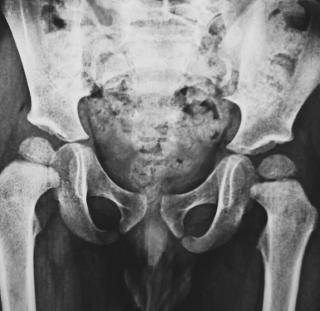

Ультразвуковое исследование является основным методом диагностики врождённого вывиха бедра у новорождённых и младенцев. Метод позволяет визуализировать анатомическое положение головки бедренной кости, структуру вертлужной впадины и оценить стабильность тазобедренного сустава. В пренатальном периоде косвенные признаки дисплазии тазобедренного сустава могут выявляться при ультразвуковом исследовании плода, но окончательный диагноз устанавливается после рождения.

УЗИ при врожденном вывихе бедра выявляет следующие анатомические признаки:

В режиме серошкального сканирования определяется несоответствие положения головки бедренной кости относительно вертлужной впадины с гипоэхогенным сигналом в зоне суставного контакта, что свидетельствует о нарушении конгруэнтности сустава.

В режиме сканирования мягких тканей определяется недоразвитие крыши вертлужной впадины с уменьшенной её высотой и гиперэхогенным сигналом по краю, что свидетельствует о диспластических изменениях сустава.

- Положение головки бедренной кости относительно вертлужной впадины, что даёт возможность оценить её центрирование, выявить латеральное или краниальное смещение и определить степень несоответствия суставных поверхностей.

- Форма и толщина вертлужной впадины, что позволяет определить степень её недоразвития, визуализировать уплощение крыши и оценить уровень диспластических изменений.

- Глубина расположения головки бедренной кости в суставе, что помогает выявить уровень её смещения, определить степень погружения в суставную впадину и оценить возможность самопроизвольного вправления.